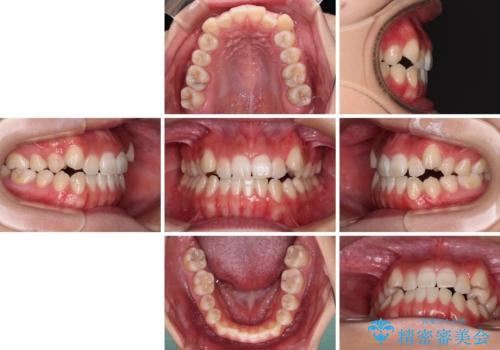

- 前歯の開咬と、上顎前歯の八重歯やデコボコを気にして来院された患者様です。

上顎歯列が狭窄していたため、急速拡大装置により上顎骨を側方に拡大し、その後ワイヤー装置にて矯正治療を行うこととしました。

上顎骨を拡大することで、八重歯やデコボコを歯列に収めることができ、下顎の歯が外に位置していた奥歯の咬み合わせも改善することができました。

スペースも短期間に獲得できるため、1年程度で治療を終えることができました。